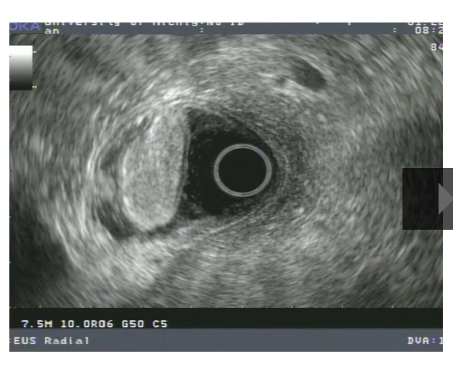

24

gastric duplication cyst